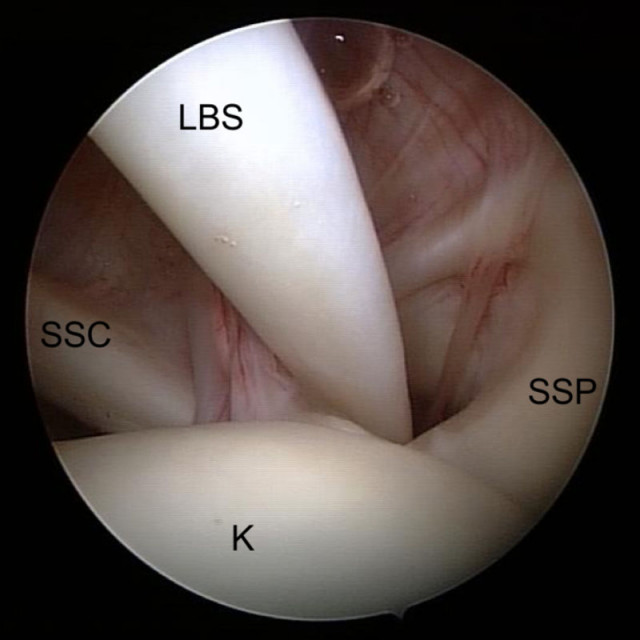

Arthroskopisches Bild einer gesunden Rotatorenmanschette (SSP)

Arthroskopisches Bild einer gesunden Rotatorenmanschette (SSP), die direkt nach dem Gelenkknorpel des Oberarmkopfes (K) ansetzt.

Der sogenannte Bizeps-Pulley: Die lange Bizepssehne (LBS) gleitet über den Oberarmkopf (K)  aus den Gelenk zum Arm hinunter. Die Sehnen der Rotatorenmanschetten-Muskeln Supraspinatus (SSP) und Subscapularis (SSC) stabilisieren zusammen mit einem Band (SGHL) den Verlauf der LBS.